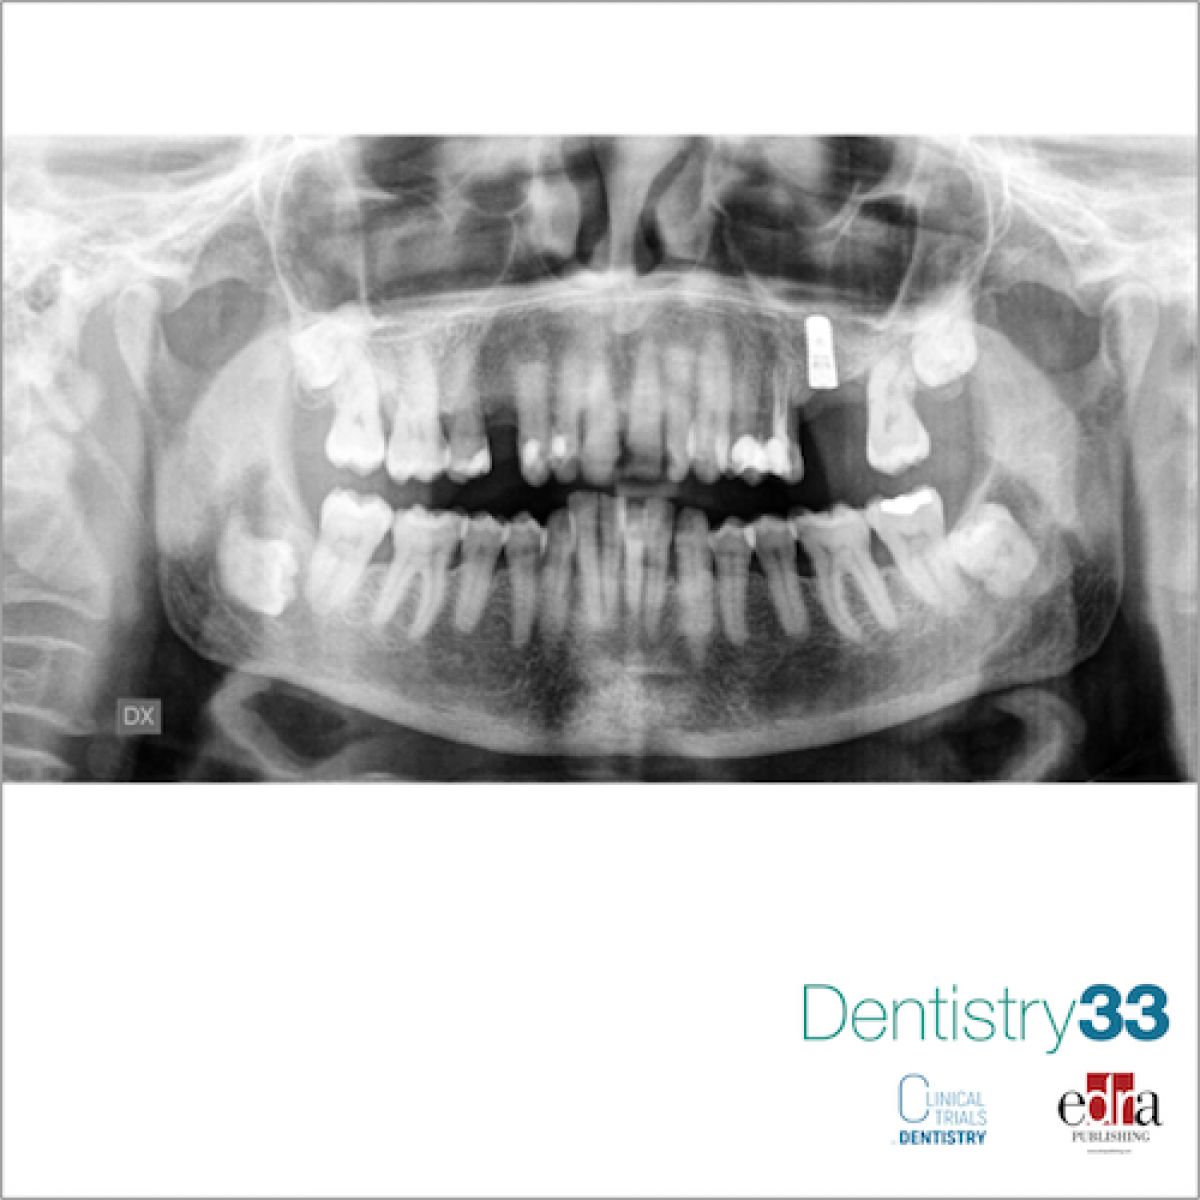

This case report is about a 45 years old woman, who came to the attention of the authors, presenting an asymptomatic osteolytic area related to her impacted wisdom tooth. The treatment chosen was marsupialization. The follow-up was as follows: the first ortopantomography and dentascan were taken at T0, than T1 corresponds at 6 months, T2 corresponds at 12 months, T3 corresponds at 18 months.

During the follow-up a progressive deposition of new bone has been observed around the impacted tooth.